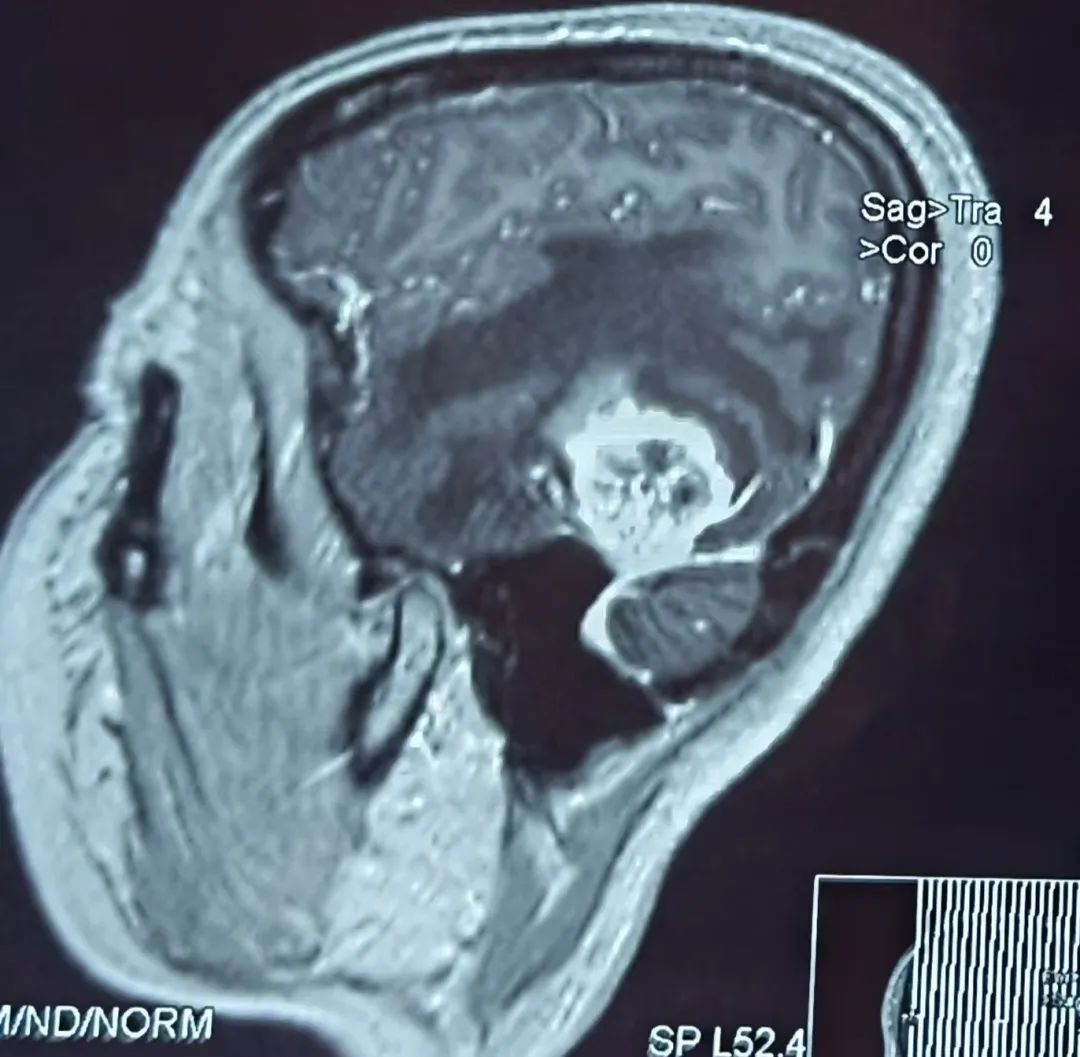

患者43岁,肾肿瘤术后一个半月开始出现头痛难忍,伴有恶心、呕吐、言语不流利,每天靠止痛药缓解头痛,到医院行头部核磁检查提示左颞叶占位,考虑脑转移瘤可能性大。为进一步诊治,在朋友的介绍推荐下,患者来到我院神经外科找到桑文渊主任。桑主任详细询问病史,仔细阅片后,初步诊断患者为脑转移瘤。

患者术前核磁影像